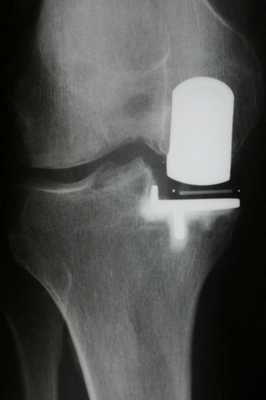

Имплант на рентгене.